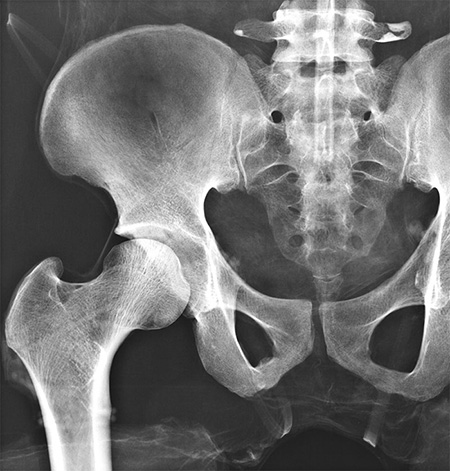

德國(guó)Erler Zimmer 7200天然骨骼全身模體,EZ 7200全身模體在世界上是獨(dú)一無二的,并為放射線攝影中的定位和對(duì)準(zhǔn)技術(shù)提供了極好的培訓(xùn)機(jī)會(huì)。它應(yīng)該是任何放射學(xué)?;驹O(shè)備的一部分。

德國(guó)Erler Zimmer 7200天然骨骼全身模體,EZ 7200全身模體包含一個(gè)真實(shí)的人體骨骼,可以像患者一樣拍攝真正的X射線圖像。使用真實(shí)的骨架可以提供最小的導(dǎo)向結(jié)構(gòu),這對(duì)于塑料骨架來說是不可能的。

在組裝這個(gè)模體時(shí),我們特別注意關(guān)節(jié)空間的正確尺寸。所有關(guān)節(jié)都可移動(dòng)地安裝,允許定位在所有正常的X射線位置。手臂可以向上移動(dòng),這使得模體適合用于CT下的各種骨質(zhì)檢查。

每個(gè)德國(guó)Erler Zimmer 7200天然骨骼全身模體,EZ 7200全身模體都是手工制作的獨(dú)一無二的; 它的尺寸和外觀可能不同。根據(jù)不同的模體,它可能有一些病態(tài),外形可能因骨架的大小而異。新版本與德國(guó)著名放射學(xué)家學(xué)校合作重新設(shè)計(jì),適合放射學(xué)領(lǐng)域所有教育需求。

This model is unique in the world and provides excellent training opportunities for positioning and alignment techniques in projection radiography. It should be part of the basic equipment of any radiographic school.

The phantom contains a real human skeleton, which allows taking real X-ray images like in a patient. Using a real skeleton provides even smallest guiding structures which is impossible with a plastic skeleton.

During assembly of this phantom we pay special attention to the correct size of joint spaces. All joints are moveably mounted allow positioning in all normal x-ray positions. The arms can be moved upwards which makes the phantom suitable for use in all kinds of osseous examinations under CT.

Each phantom is hand-made one of a kind; it may differ in size and appearance. Depending on the individual phantom it may have some pathologies, outer shape may differ depending on size of the skeleton. The new version was re-designed in co-operation with a well-known German school for radiographers and fits all needs for education in radiography.